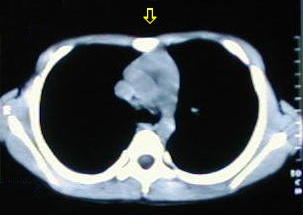

• Corte a nivel del apéndice sifoides, observe la acentuada depresión por efectos de los cartilagos costales comunes.

• A nivel de la base del tórax los extremos de los arcos costales se observan protruyentes, debido al cambio de dirección de los cartílagos, ellos generalmente ceden, al resecar los cartílagos costales comunes.

• Las estructuras mediastinales se alojan en un tórax que ha disminuido su diámetro antero-posterior por la depresión esternal y la marcada concavidad de la columna dorsal.